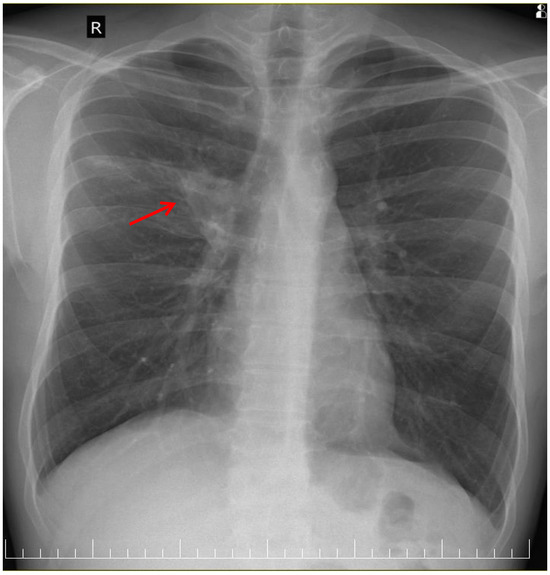

A posteroanterior chest radiography (chest X-ray) before admission revealed a high-intensity opacity with indistinct margins and a heterogeneous appearance, localized in the right suprahilar region (Figure 1). Subsequent native and contrast-enhanced chest computed tomography scans (CT) identified centrilobular micronodules and consolidations associated with linear lesions that showed a characteristic “tree-in-bud” pattern in the right upper lobe, along with fluid accumulation in the right pleural cavity, suggestive of secondary pulmonary TB or other infectious ethiology (Figure 2).

Figure 1. Chest X-ray showing high-intensity opacity in right suprahilar region (red arrow).